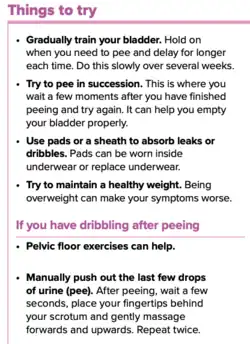

Lifestyle

Lifestyle alterations to address the symptoms of BPH include physical activity,[59] decreasing fluid intake before bedtime, moderating the consumption of alcohol and caffeine-containing products, and following a timed voiding schedule.

Patients can also attempt to avoid products and medications with anticholinergic properties that may exacerbate urinary retention symptoms of BPH, including antihistamines, decongestants, opioids, and tricyclic antidepressants; however, changes in medications should be done with input from a medical professional.[60]